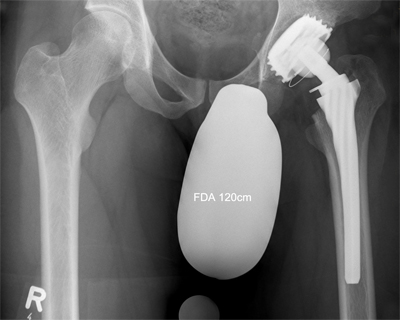

Ein Beispiel: 34 –jähriger Patient mit Morbus Perthes

( Absterben des Hüftkopfes im Kindesalter )

Hier ist der obere Anteil des Knochens bereits durch schmerzbedingte Entlastung osteoporotisch. Die höhere Sicherheit des Einwachsen des Schaftes bringt die Prothese in Standardmaß